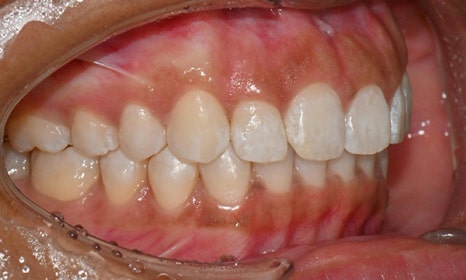

교정 마무리 후 사진 (2025.8)

교정 마무리 후 사진으로 위아래 치아 배열이 개선되었고 공간이 모두 닫혔습니다. 위아래 앞니가 깊게 물리는 과개교합도 처음에 비하여 많이 개선되었습니다. 다만 아래 작은 어금니 배열로 인하여 왼쪽 어금니 교합은 아직 완벽하지 않은 상태로, 추후 본국으로 돌아가서 자료를 transfer 해드려서 이어서 치료를 받기로 하셨습니다.

위 오른쪽 앞니의 경우 초진시에도 틀어져있던 부위의 잇몸이 내려가 있었으므로, 치아가 배열되면 좌우 잇몸 높이가 맞지 않을 것임을 미리 고지시켜드렸었고, 추후 치은성형술로 잇몸 높이를 맞추는 것이 심미적으로 더 보기 좋을 것임을 추천드렸습니다.